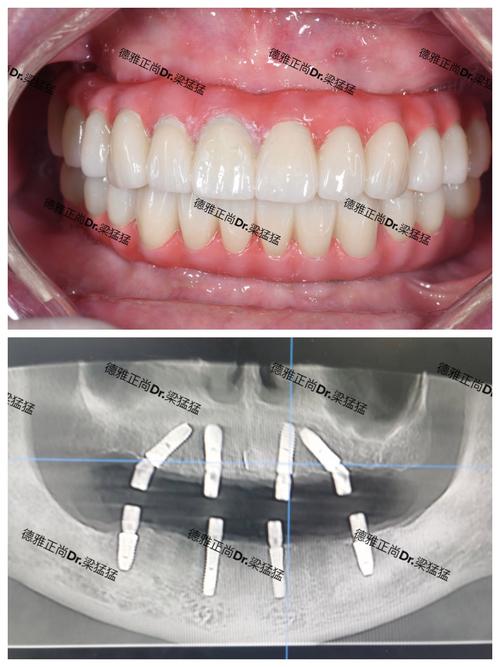

韩国种植牙的流程与常规种植类似,主要包括术前检查、植入种植体、骨结合、安装基台和戴牙冠五个步骤,术前需进行口腔CT检查,评估牙槽骨密度、高度及神经血管位置;植入种植体在局部麻醉下进行,手术时间约30-60分钟;骨结合期间需避免种植体受力,保持口腔卫生;3-6个月后,安装基台并取模制作牙冠;最后试戴调整,完成修复,部分患者若骨条件良好,可选择即刻种植或即刻负重技术,缩短治疗周期。